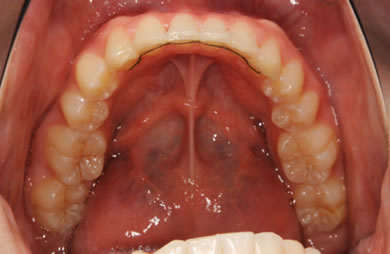

| 性別/年齢 | 女性 / 19歳 | ||||||||||||||||||||||||||||||||

| 主訴 | 上のデコボコの歯を綺麗にしたい。 | ||||||||||||||||||||||||||||||||

| 治療方針 | 上顎の歯の傾斜を正常に治す事で下顎を正常な位置に推進させ、非抜歯にて治療を行う。また、上下の顎のずれの治療のため、装置にゴムを使用し審美的・機能的に良い咬合を獲得させる。 | ||||||||||||||||||||||||||||||||

| 治療内容 | 唇側矯正(シルバー) | ||||||||||||||||||||||||||||||||

| 総治療費 | 659,300円 | ||||||||||||||||||||||||||||||||

| 治療期間 | 1年9ヶ月 |